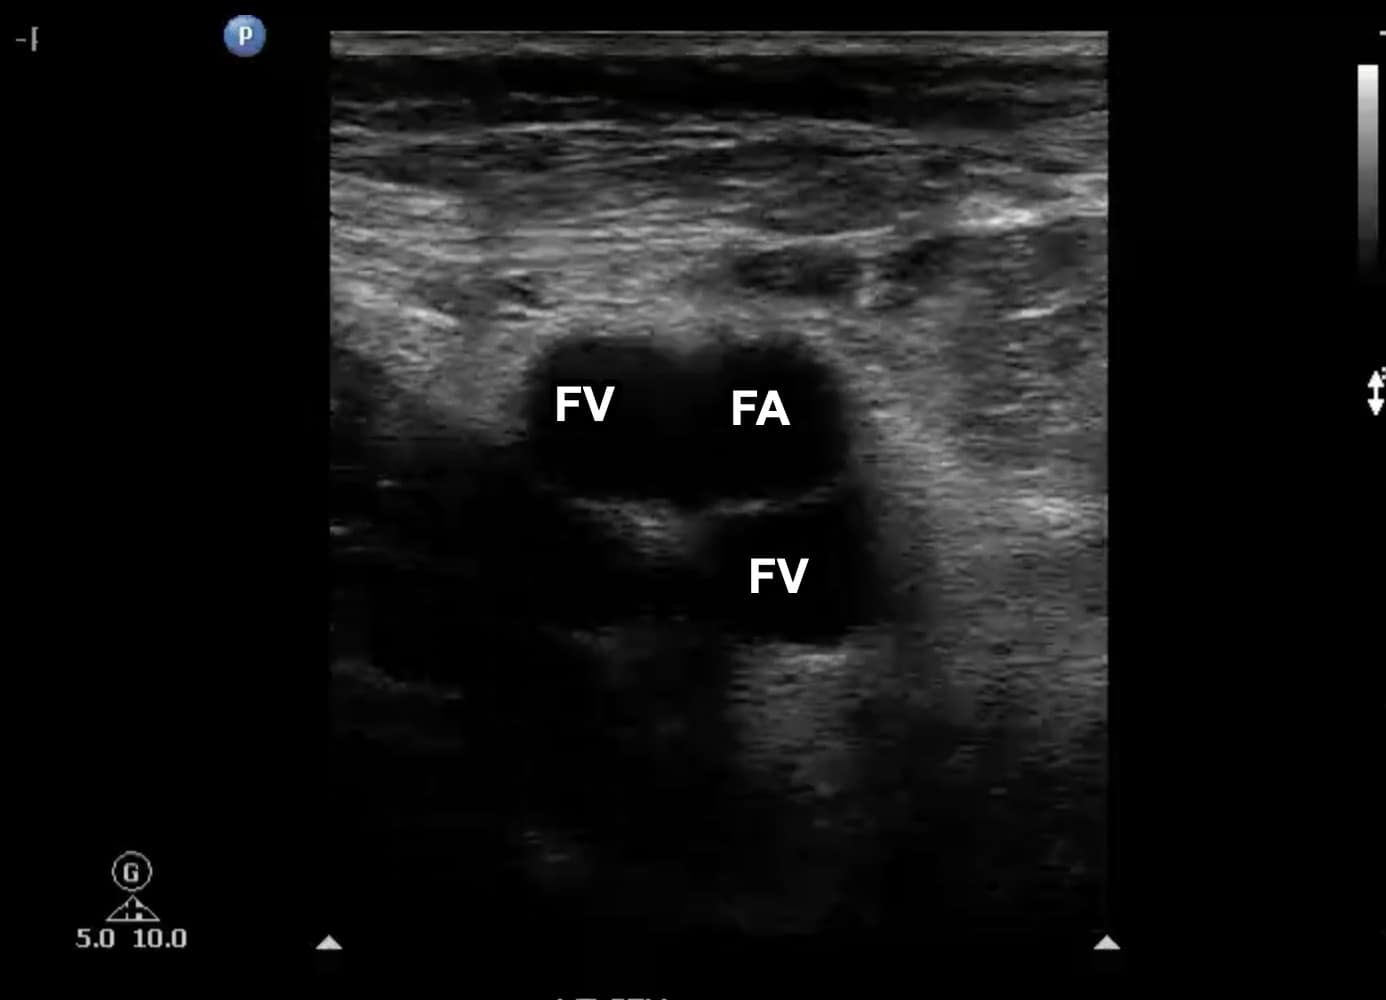

Once at the CFV/FV junction, it is important to look for evidence of venous duplication. Venous duplication occurs in a significant number of patients and is seen most commonly in the region of the FV and PV (Figure 7). Failure to identify venous duplication could lead to missing a DVT that occurs in only one of the systems. The FA is seen anterior to the FV in this region (Figure 8). As the FV approaches the adductor canal, an anterior approach utilizing an increased field of depth can also be used to better visualize the vein. Compression at this level is done by placing the freehand posteriorly and squeezing since transducer pressure will not result in venous compression with this approach (Figure 9).

Figure 7. Transverse window at level of left femoral vein (FV) with duplication noted. Note that one branch is medial to the femoral artery (FA) and the other is posterior.

Figure 8. Split screen demonstrating transverse window of the mid-femoral vein (FV). Note that the FV is located deep to the femoral artery (FA). The deep femoral artery (DFA) and deep femoral vein (DFV) can no longer be visualized.